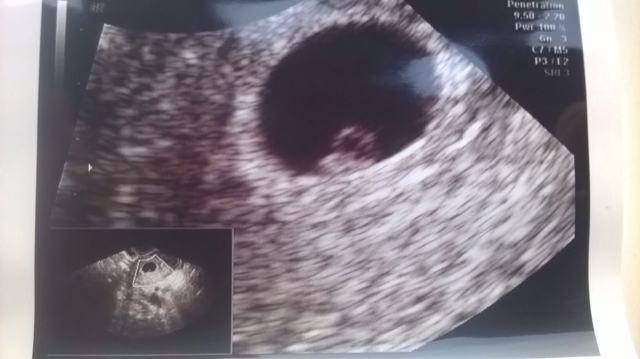

maleństwo ma 4mm, idealny 6 tydzień i już bije serduszko, wszystko w jak najlepszym porządku

uff spora ulga